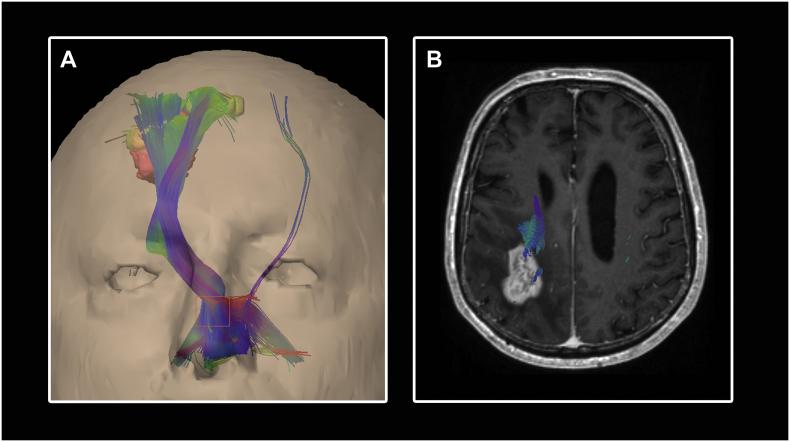

Navigated transcranial magnetic stimulation (nTMS) combined with diffusion tensor imaging (DTI) is used preoperatively in patients with eloquent-located brain lesions and allows analyzing non-invasively the spatial relationship between the tumor and functional areas (e.g. the motor cortex and the corticospinal tract [CST]). In this study, we examined the diffusion parameters FA (fractional anisotropy) and ADC (apparent diffusion coefficient) within the CST in different locations and analyzed their interrater reliability and usefulness for predicting the patients' motor outcome with a precise approach of specific region of interest (ROI) seeding based on the color-coded FA-map.

Prospectively collected data of 30 patients undergoing bihemispheric nTMS mapping followed by nTMS-based DTI fiber tracking prior to surgery of motor eloquent high-grade gliomas were analyzed by 2 experienced and 1 unexperienced examiner. The following data were scrutinized for both hemispheres after tractography based on nTMS-motor positive cortical seeds and a 2nd region of interest in one layer of the caudal pons defined by the color-coded FA-map: the pre- and postoperative motor status (day of discharge und 3 months), the closest distance between the tracts and the tumor (TTD), the fractional anisotropy (FA) and the apparent diffusion coefficient (ADC). The latter as an average within the CST as well as specific values in different locations (peritumoral, mesencephal, pontine).

Adding diffusion weighted imaging derived information on the structural integrity of the nTMS-based tractography results improves the predictive power for postoperative motor outcome. Utilizing a second subcortical ROI which is specifically seeded based on the color-coded FA map increases the tracking quality of the CST independently of the examiner's experience. Further prospective studies are needed to validate the nTMS-based prediction of the patient's outcome.

经颅磁刺激导航(nTMS)联合弥散张量成像(DTI)用于语言功能区脑病变患者的术前评估,可无创性分析肿瘤与功能区(如运动皮质和皮质脊髓束 [CST])之间的空间关系。在这项研究中,我们检查了 CST 内不同部位的弥散参数 FA(各向异性分数)和 ADC(表观弥散系数),并分析了它们的观察者间可靠性,以及基于彩色 FA 图进行特定 ROI 种子特异性区域分析对预测患者运动结局的作用。

前瞻性收集了 30 例双侧 nTMS 映射后接受 nTMS 引导下弥散张量纤维追踪术的运动功能区高级别胶质瘤患者的资料,由 2 名有经验的和 1 名无经验的检查者进行分析。在基于 nTMS 运动皮质阳性种子的束追踪后,根据彩色 FA 图定义的第 2 个 ROI(脑桥尾侧 1 层),对双侧数据进行研究:术前和术后运动状态(出院日和 3 个月)、束与肿瘤的最短距离(TTD)、各向异性分数(FA)和表观弥散系数(ADC)。后者作为 CST 内的平均值以及不同部位(瘤周、中脑、脑桥)的特定值。

在基于 nTMS 的束追踪结果的结构完整性上添加弥散加权成像信息可提高对术后运动结局的预测能力。利用基于彩色 FA 图特异性种子的第二个皮质下 ROI,可提高 CST 的追踪质量,而与检查者的经验无关。需要进一步的前瞻性研究来验证基于 nTMS 的患者预后预测。